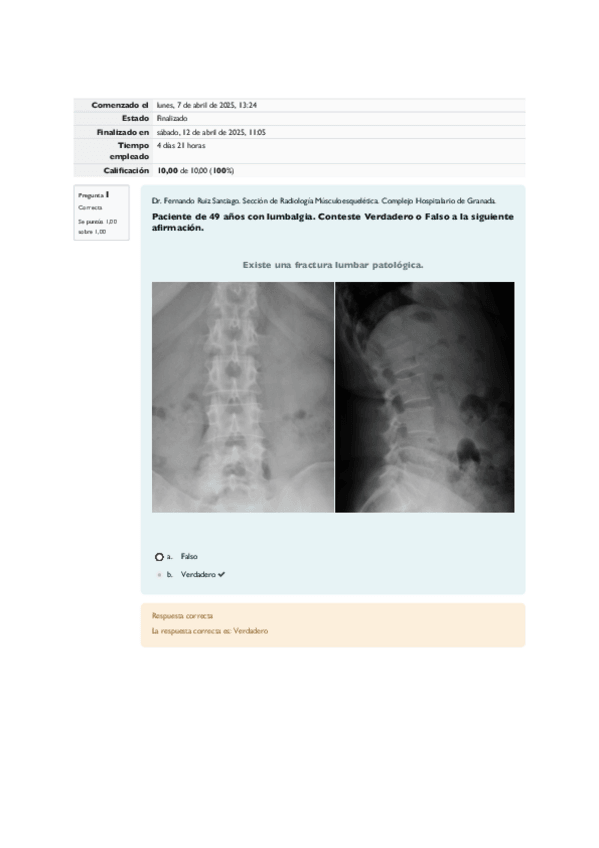

CASO CLÍNICO RADIOLÓGICO DE LA SEMANA. Músculo-esquelético. Dr. Ruiz Santiago.

12 páginas

Casos-clinicos-musculo-esqueletico-2025.pdf